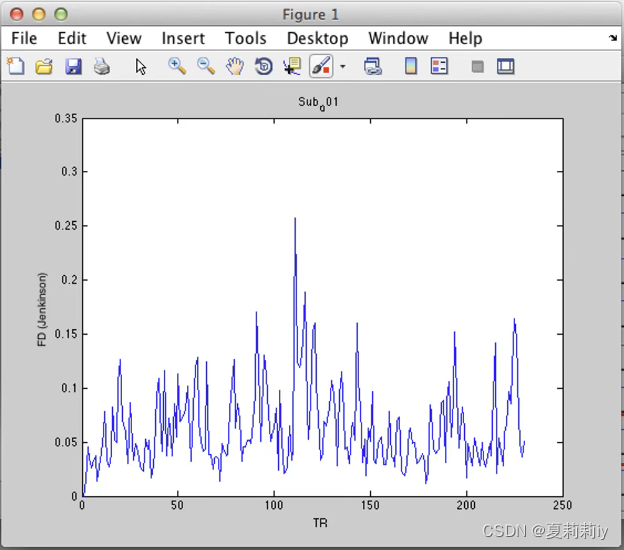

(8)Motion Report

①显示MeanFD

②再点击view显示被试头动大小